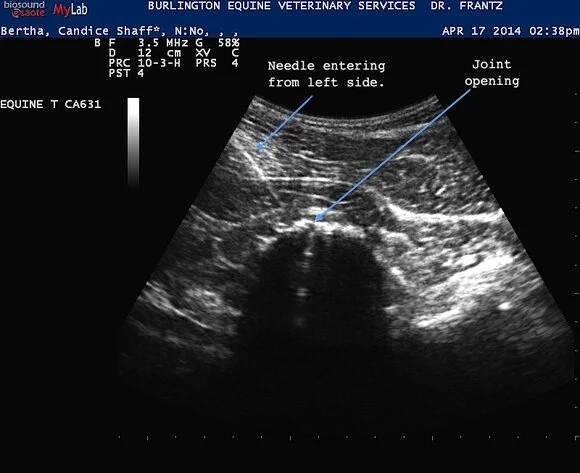

Most of the cases I see are more like what was seen in the previous x-rays and fortunately they are much more amenable to treatment. Just to show you what the treatment looks like here are two ultrasound images of a needle that I am using to inject that’s being guided to the vertebral joint. Ultrasound allows the visualization of the affected structures and at the same time provides real time images as I can see where the needle will be placed.

bertha120140417143141_1438192_1.jpg

bertha2__20140417143141_1438190_1.jpg